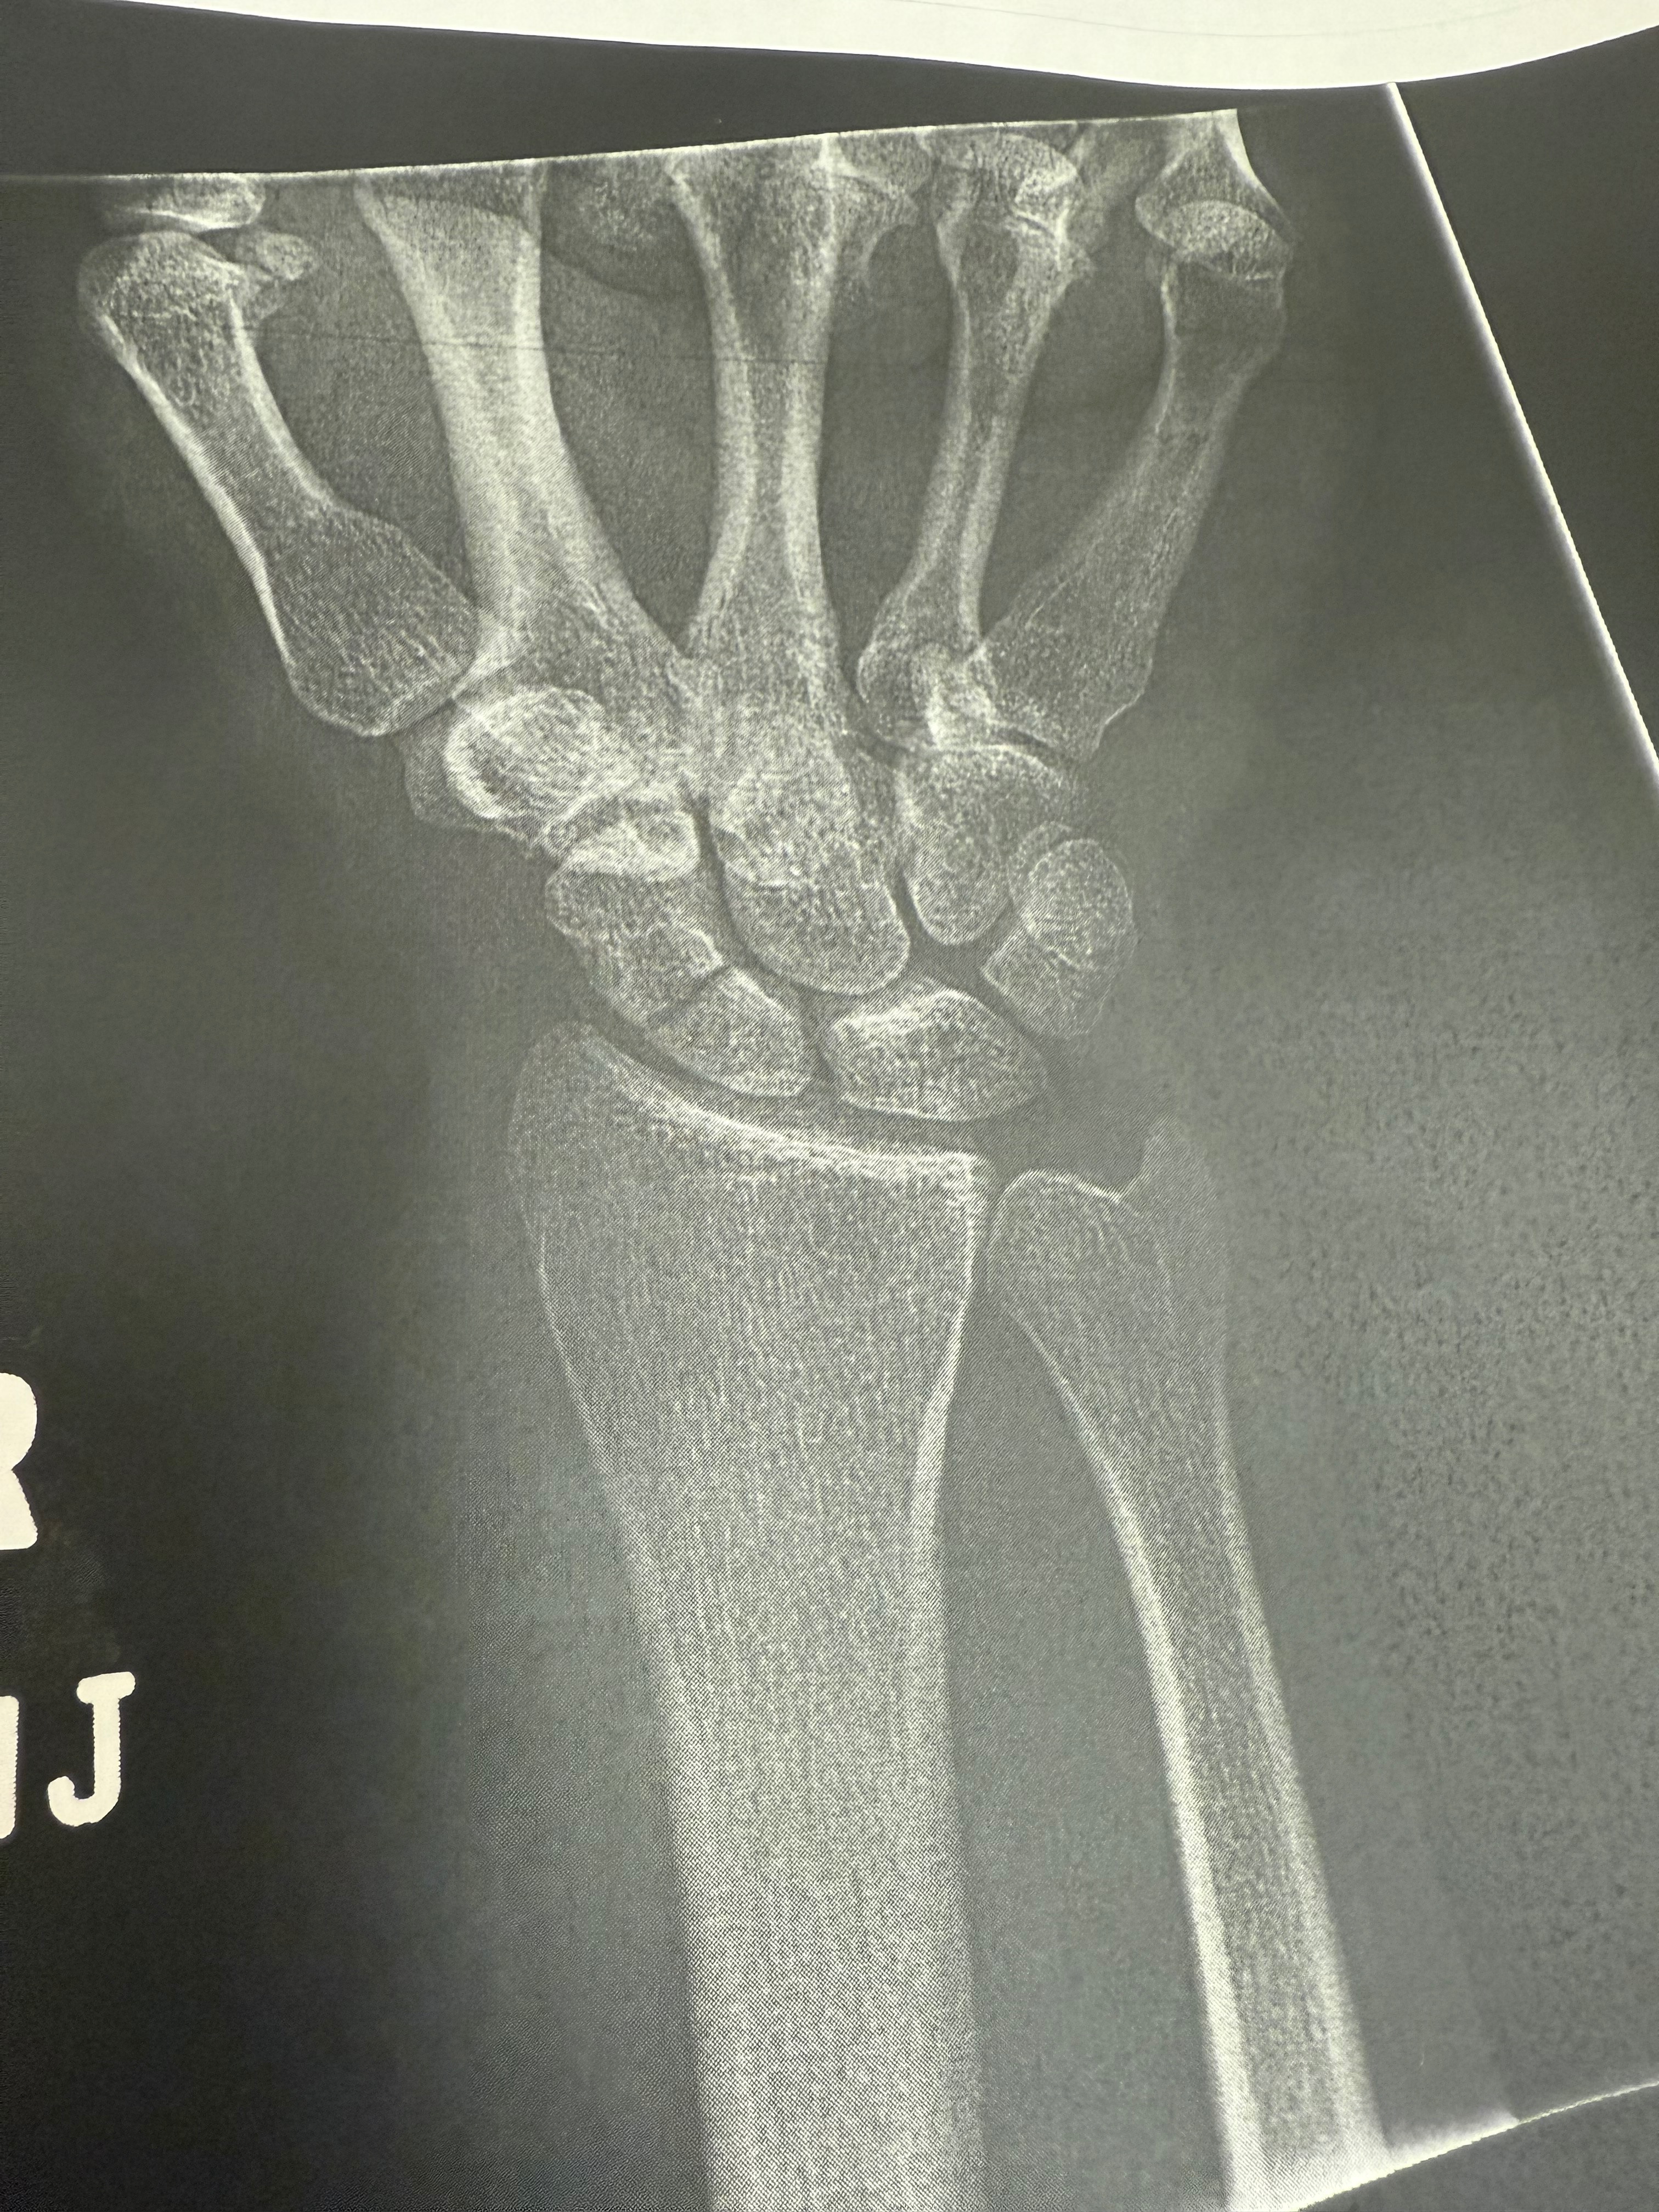

On Friday 5-23-25 someone pulled out infront of Taber causing him to wreck his motorcycle. He luckily survived with minimal injuries but does have a broken wrist, ankle, and road rash. Due to injuries Taber will be out of work for the foreseeable future. As he was the sole provider this has left us in a rough spot. While I am working now it’s not enough to keep us afloat causing us to ask for this extra help.

6-3-25 Update- Taber had surgery today on his wrist and all went well. He’s now at home resting.